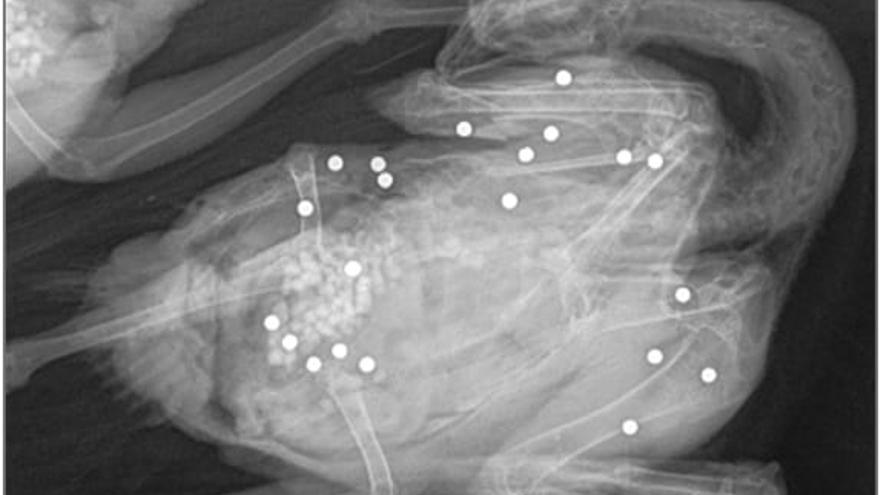

El muestreo se realizó con arma de fuego (escopeta) empleando munición libre de plomo, concretamente munición de acero, al objeto de evitar una posible confusión a la hora de determinar el origen de los perdigones “sospechosos” de haber sido ingeridos y encontrados en buche, molleja o intestinos. Se apunta que “al emplear munición de acero en el muestreo en aquellas zonas donde únicamente se utiliza la munición de plomo, garantiza que la presencia de perdigones de acero en el aparato digestivo de las aves muestreadas tiene su origen únicamente en el disparo y que cualquier perdigón de plomo encontrado no es causa del mismo”. Otro posible error que se evita es la posible contaminación de las muestras al emplear munición de plomo para el muestreo. Se pone de manifiesto que “a lo largo de los diferentes estudios recogidos en la bibliografía científica, el empleo de la munición de plomo ha sido, con carácter general, el método seguido para la obtención de las muestras, hecho que ningún autor parece haber puesto en duda y que de algún modo podría poner en tela de juicio esta metodología de muestreo”.

A la vista de los resultados, se pone de manifiesto que la presencia de perdigones de plomo “sospechosos” de haber sido ingeridos por las especies muestreadas se reduce significativamente con respecto al informe de 2019, apareciendo únicamente un ejemplar de perdiz roja aclimatada con perdigones de plomo en la molleja, con la certeza de haber sido ingeridos. No se encontró ningún ejemplar con perdigones de plomo en buche o intestinos. Con respecto a las concentraciones de plomo en hígado los valores encontrados se podrían calificar de muy bajos, estando por debajo de la media de la bibliografía científica consultada.